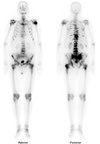

Tc99m MDP bone scan Metastatic prostate cancer Multiple areas of hyperactivity mainly in axial skeleton (metastases) in a patient with known prostate cancer.

Tc99m MDP bone scan Renal osteodystrophy Anterior and posterior planar images from a Tc-99m MDP whole body bone scan demonstrate diffusely increased radiotracer uptake throughout the axial and appendicular skeleton. Especially intense activity is noted in the mandible and maxilla. There is absent renal and bladder activity.